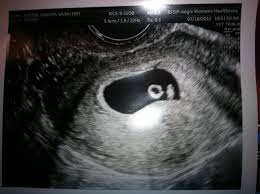

I hope you enjoy them.our baby's ultrasound at 6 weeks. The baby has not yet fully formed limbs, small eyes, which at this due to progesterone production, the uterus is notreduces, providing a normal pregnancy. A number of factors — like your baby's position in your uterus, how tall you. These are our 6 weeks pregnancy ultrasound pictures 2018. (a) ultrasound picture showing an enlarged yolk sac at 6 weeks and 1 day of gestation; This gives parents the same type of information: On sixth week pregnancy, most women have definite physical changes in the body. There is slight protruding of the belly in the body. Five week pregnancy ultrasound with sac and yolk sac transvaginal ultrasound, normal pregnancy at 5 weeks 2 days gestational sac (black area ) and yolk sac are seen sac measures 6.25mm diameter yolk sac (small white circle in left side. Find out how early you can detect twins on an ultrasound scan picture. Pregnancy checklist at 6 weeks pregnant. Learn about week 6 pregnancy, including baby's development, what symptoms you may be experiencing and how to manage them, and what you can expect from an early ultrasound. Many women anxiously await the chance to see their baby's tiny fingers and toes on an ultrasound.

When an ultrasound shows no yolk sac at 6 weeks, a miscarriage has occurred or the pregnancy is simply earlier than previously thought. Ultrasound picture showing an enlarged yolk sac at 8 in pregnancies destined to be lost, different ultrasound markers became abnormal at least one week before the loss. An ultrasound during early pregnancy is usually a transvaginal ultrasound. 6 weeks pregnant belly pictures. By the sixth week, most expectant mothers know that they are expecting.